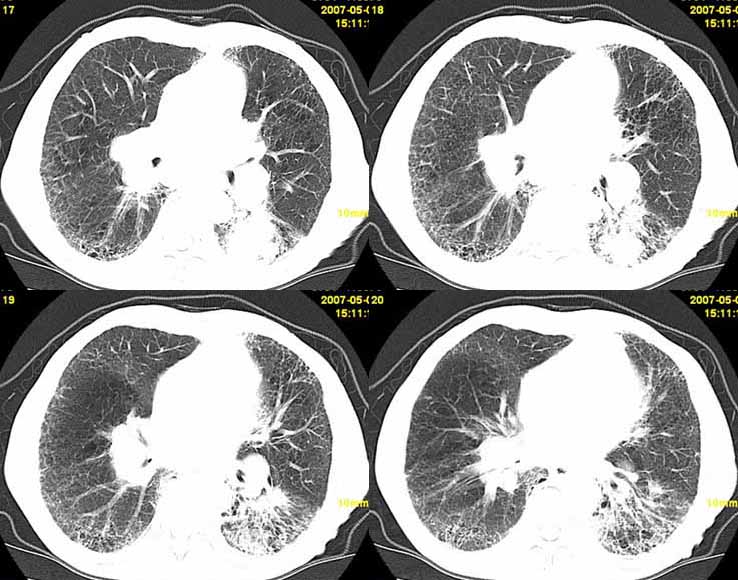

以下是引用小初学者在2007-5-12 11:09:00的发言:[br][br]双肺弥漫性质纤维化(考虑矽肺所致),并发左肺下叶背段周围性肺癌纵隔淋巴转移。

以下是引用zhangzhongshou在2007-5-12 12:09:00的发言:[br]1、左下叶背段周围型肺癌左肺门及纵隔淋巴结转移可能性大。[br]2、弥漫性肺气肿(双侧)。[br]3、双肺间质纤维化。

以下是引用老爱克斯新网客在2007-5-12 12:54:00的发言:[br]1周围型肺癌纵隔肺门淋巴结转移,2肺间质纤维化,